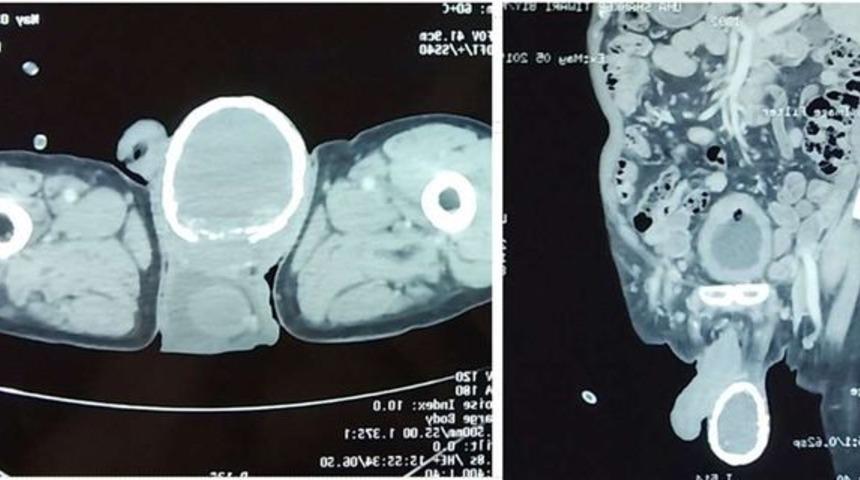

Hindistan'da ismi açıklanmayan bir adam boşaltım sorunları nedeniyle doktora gitti. Adamı muayene eden üroloji uzmanı doktor adamın testislerinin birinin yumurta kabuğu gibi kireçle kaplandığını ortaya çıkardı. Tetkiklerin neticesinde ise bu sorunun sivrisinek ısırmasının yol açtığı enfeksiyon nedeniyle olduğu belirtildi.

Doktor idrar yolu enfeksiyonu semptomları gösteren adamı muayene etti. Ancak bu muayene sonucunda adamın bir testisinin yumurta kabuğu gibi kireçle kaplandığı ortaya çıktı.

Elle muayenede ise adamın bir testisinin taş gibi sertleştiği ortaya çıktı. Doktor bunun sivrisinek larvalarından kaynaklandığını adamın muhtemelen bir sivrisinek tarafından ısırıldığını öne sürdü.